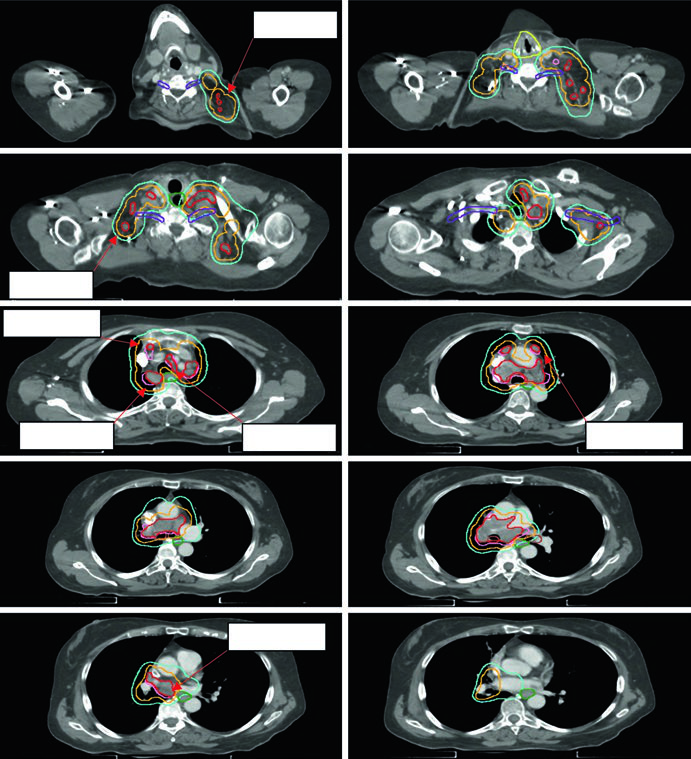

CPPC: irradiação de campo envolvido em doença limitada e extensiva

O carcinoma de pequenas células apresenta radiorresistência relativa e crescimento rápido, mas é sensível à irradiação combinada à quimioterapia. A abordagem de campo envolvido é aceita em ambos os estádios.

A expansão GTV → CTV no CPPC é de 0,5 a 1,0 cm, frequentemente incluindo o hilo ipsilateral mesmo sem captação PET demonstrada, dado o padrão de drenagem linfática. As margens CTV → PTV seguem as mesmas diretrizes do CPNPC, calibradas pelo sistema de IGRT disponível.

Os esquemas de dose diferem por estádio:

- Estádio limitado: 45 Gy em 1,5 Gy duas vezes ao dia (30 frações) — o esquema clássico de Turrisi — ou 66–70 Gy em 2,0 Gy diário como alternativa de dose mais alta

- Estádio extensivo (consolidação): 30–45 Gy em 3,0 Gy/fx no sítio de doença volumosa

A Figura 13.6 mostra um caso cT2N2 de estádio limitado com o campo envolvido cobrindo tumor primário e linfonodos mediastinais comprometidos, mas excluindo cadeias eletivas. O esquema utilizado foi 45 Gy/30fx BID.